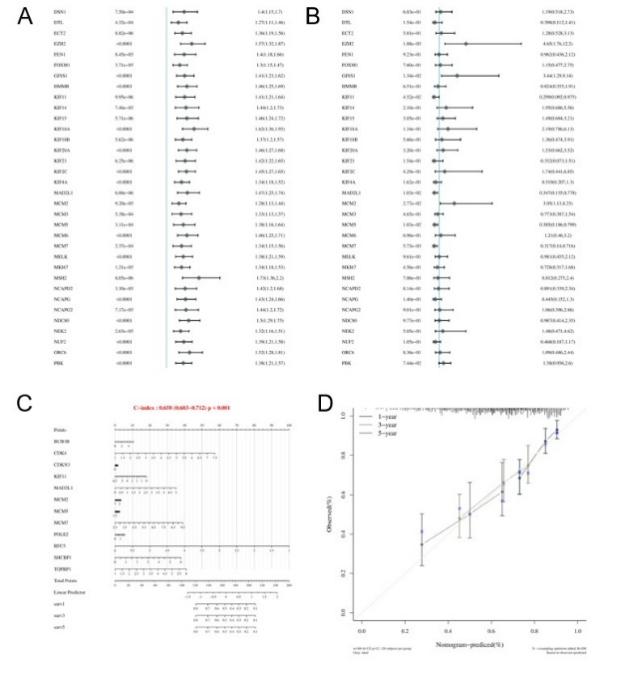

We performed survival analysis on the DEGs, indicated that the majority of these genes were associated with poor prognosis. Specifically, EZH2, GINS1, and MCM2 (Figure 6) were found to be adverse prognostic markers even after adjusting for covariates, while ALDH2, ADH4, CYP2C9, APOF, and PON1 were identified as favorable prognostic factors after covariate adjustment (Figure 7). Using both univariate and multivariate analyses, we identified variables suitable for inclusion in a Nomogram. If a gene displayed significant differences in both univariate and multivariate analyses, it was regarded as independent of other clinical factors. The Nomogram model demonstrated good predictive performance, as evidenced by its close alignment with the calibration curve.

In the Nomogram plot, a line segment with a scale represents each variable, indicating the range of possible values for that variable, while the segment's length reflects how much that factor influences the prognostic outcome. On the 'Point' axis, you can see the score for each variable, and the 'Total Point' axis indicates the overall score obtained by adding up the individual scores, with satisfactory predictive accuracy.